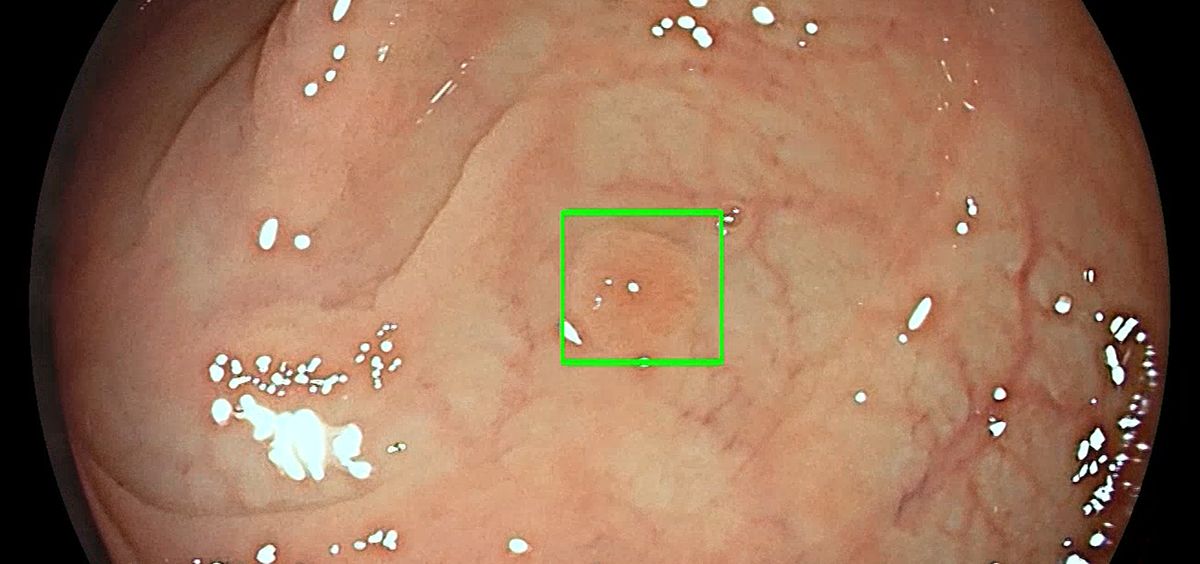

El Grupo HLA ha incorporado un sistema que utiliza la inteligencia artificial para la detección de pólipos colorrectales durante la realización de una colonoscopia. Medtronic, líder mundial en tecnología médica, ha desarrollado esta tecnología que detecta lesiones precancerosas con un marcador visual en tiempo realque funciona como un segundo observador.

“Medtronic dedica especial atención a la prevención del cáncer colorrectal mediante la detección precoz de pólipos precancerosos con tecnologías asistidas por IA", señala Giovanni Di Napoli, vicepresidente y director general de la unidad de Gastrointestinal y Hepatología de Medtronic. "Nuestro sistema detecta los pólipos automáticamente, incluso pequeños pólipos planos que pueden pasar desapercibidos, aumentando así la precisión y reduciendo el riesgo de cánceres de intervalo, que se pueden producir entre colonoscopias", declara Di Napoli.

El doctor Víctor Aguilar, resposable médico de la Unidad, afirma que “esta tecnología permite una mayor detección de lesiones polipoideas y cáncer de colon en estados iniciales, pudiendo realizar tratamientos endoscópicos avanzados sin tener que recurrir a la cirugía tradicional”.